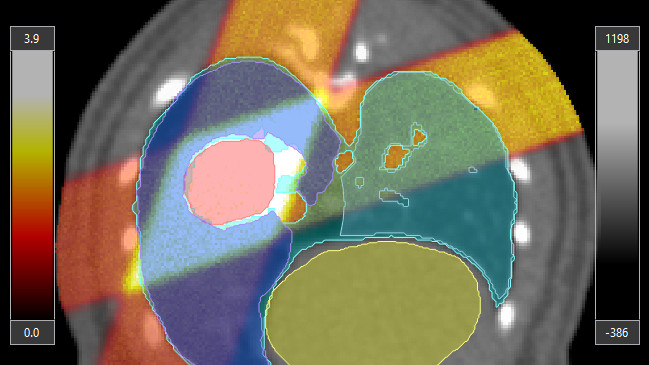

Yes. Multiple preclinical CT, MR, PET, Optical Tomography, and SPECT formats can be imported as secondary 3D image data volumes. While a primary planning CT image is mandatory, secondary image data volumes can be manually registered to the primary CT image and used during segmentation and planning to define points and volumes of interest.